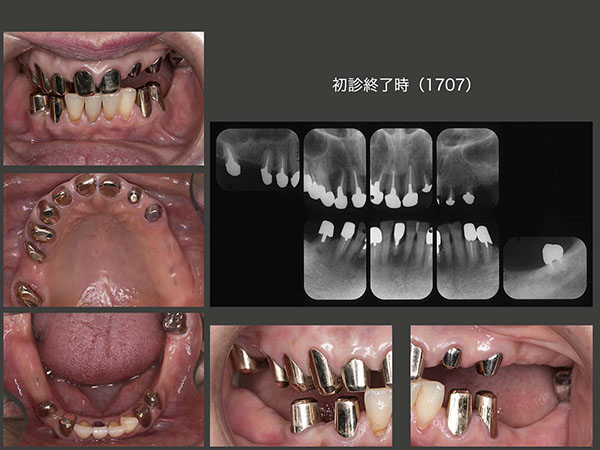

2017年7月,最終補綴装置であるコーヌス義歯を装着した.スライドは,内冠装着時.歯周ポケットは,すべて3mm以下である.下顎右奥の顎堤が窪み状に吸収しているが,これは右下8の抜歯時期が遅かったことに起因する.どうしても保存できない歯は,可及的速やかに抜歯すべきである.

コーヌス義歯装着時の状態.上顎は口蓋を抜いているので装着感がよく,発音障害もでない.下顎も大連結装置(リンガルバー)を省いたため,装着感が向上した.左下8に当初クラスプを付与したが,上顎の義歯床とクラスプアームとで頰を咬んでしまい,仕方なく除去した.治療費を抑えるためにクラウンを装着し,クラスプを使用したが,ここも最初からコーヌス冠を用いれば良かった.